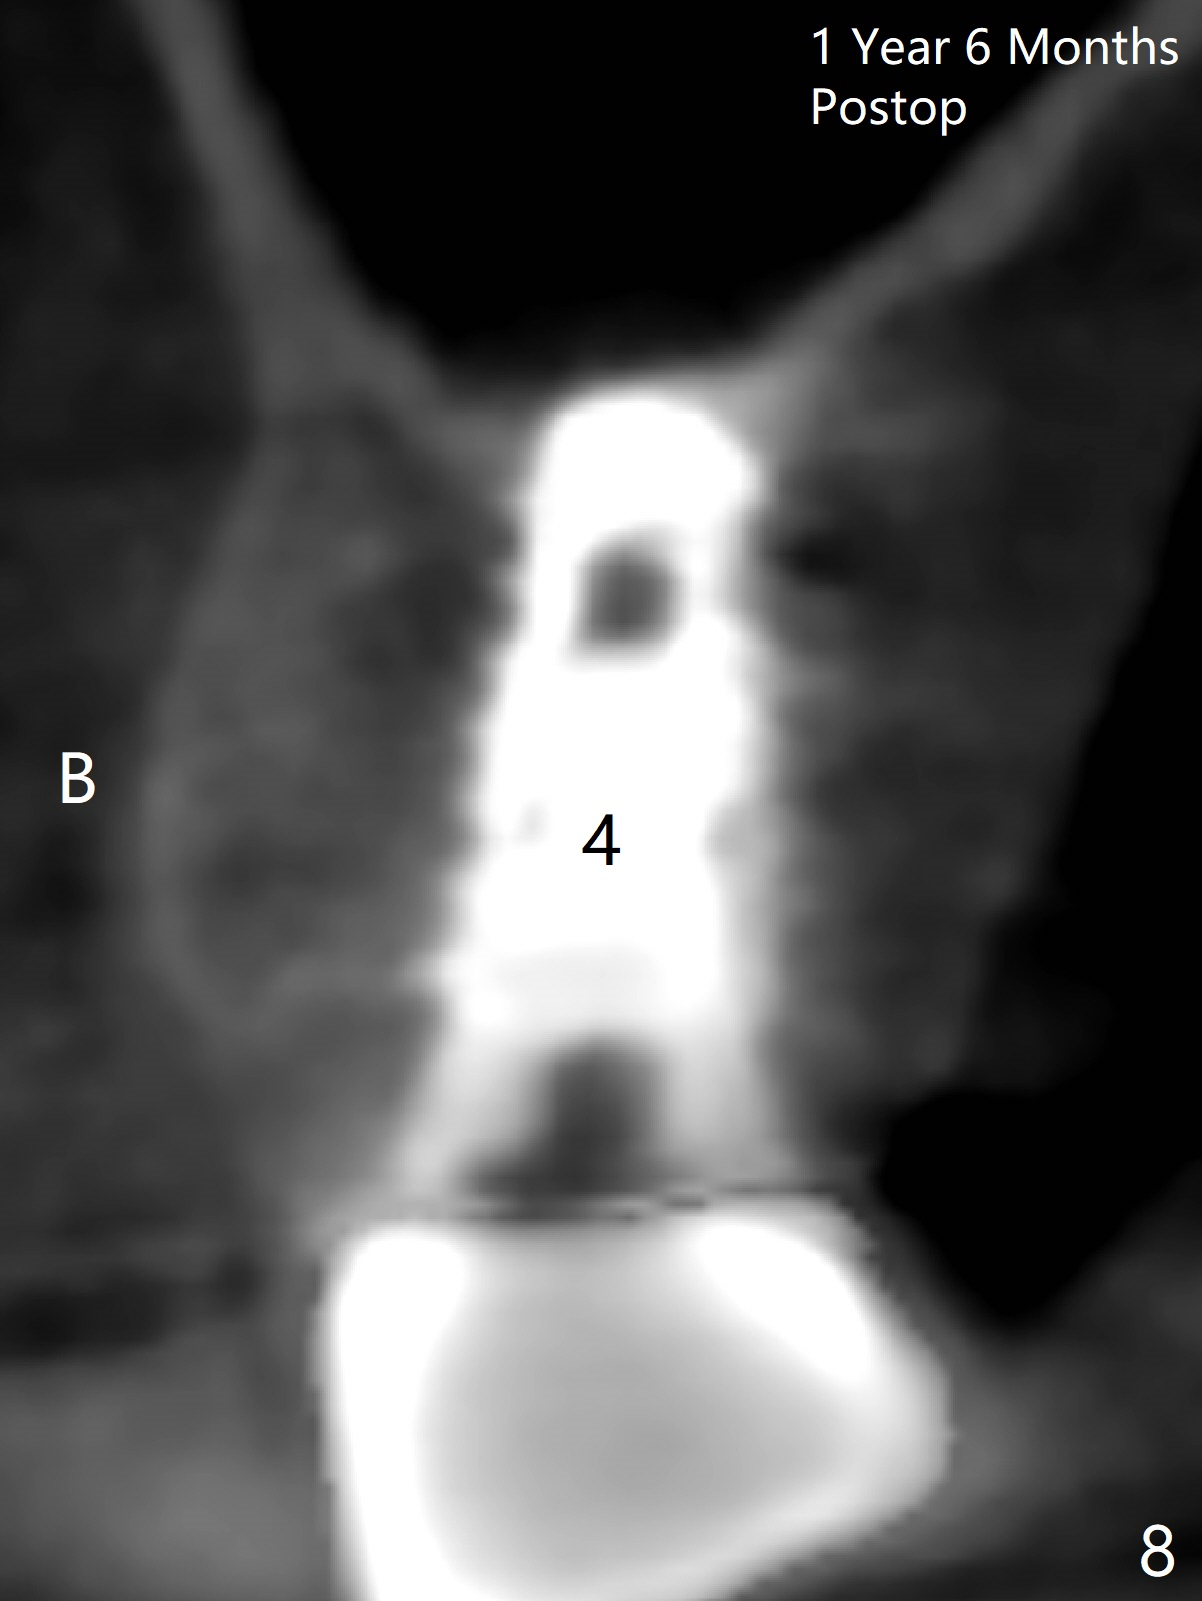

The buccal plate of the socket of #4 is thin and short (Fig.1, 5B (coronal section of the socket) red area) with apical perforation (Fig.5B >). Osteotomy at #4 starts with 1.6 mm drill in the palatal slope (Fig.2 circle; Fig.5C blue arrow), while that at #5 with Magic Split (Fig.2 black line). In fact sinus perforation occurs with the 1.6 mm drill. Osteotomy increases by using Magic Drills sequentially (2.8 and 3.3 mm) at #4 and Magic expander (3.0 mm) and the same Magic Drills at #5 (Fig.3). A 4x11 mm dummy IBS implant is placed with insertion torque of 45 Ncm at #4 with apparently intruding into the sinus (Fig.3). When a 4.5x9 mm implant is placed, the insertion torque is actually reduced (<35 Ncm, Fig.4). As osteotomy or implant diameter enlarges, it shifts buccally with less bone contact buccally (Fig.5D, as compared to Fig.5C)). In brief, once a dummy implant has achieved a reasonably high stability, do not over seat it. A small immediate implant may have more solid bone contact.

At the healed site (#5), insertion torque of a 4x11 mm implant is >50 Ncm (Fig.4). Because of supraeruption of the tooth #28 (Fig.6 arrow), a healing abutment (4x2 mm) is placed at #5 (data not shown), while a pair abutment (4.5x4(2) mm) is placed at #4 (Fig.4,6). In fact a splinted provisional is placed at #4 and 5 with a low occlusal table. There is no apparent bone loss 1 years 5 months postop (Fig.7). In fact the implants either perforate the palaatal or buccal (B) plate, as revealed by CBCT (1 year 6 months postop, immediately post cementation, Fig.8,9). It appears necessary to have guided surgery and smaller implant in the narrow ridge.